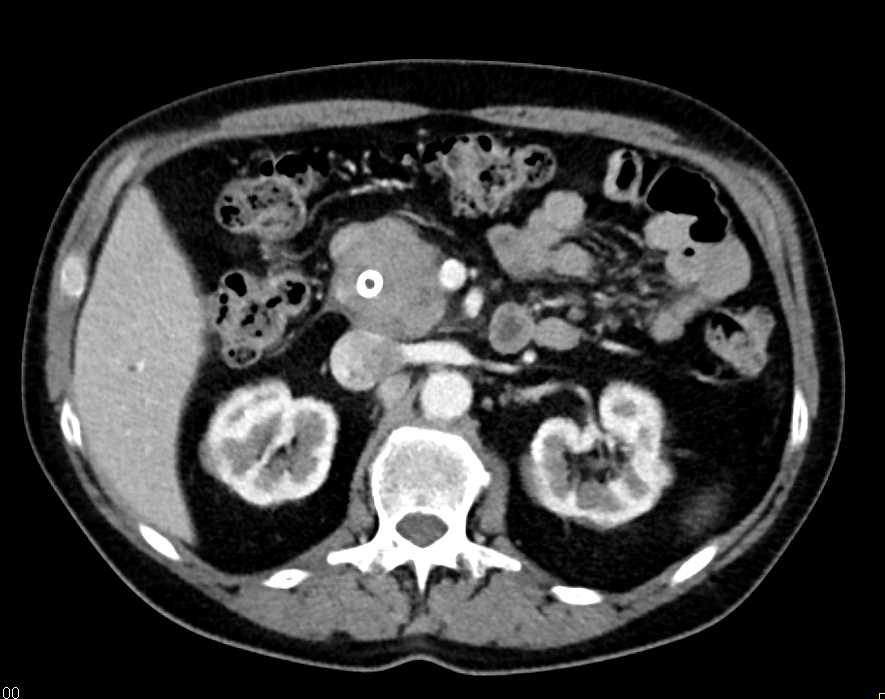

Pancreatic Neuroendocrine Tumor